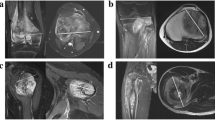

For the definition of volumes of interest (VOIs), we first drew a rough demarcation of the tumour using a polygonal VOI line. After smoothening the tentative VOI in order to generate more anchor points for the subsequent fine-tuning, the investigator moved every anchor point onto the supposed true tumour margin. If available, we also took additional imaging sequences and triplanar views into account. Figure 1a shows a single VOI line of the same tumour before and after chemotherapy.

a A single VOI line in a Salzer-Kuntschik grade I tumour located in the right tibial head before (left) and after neoadjuvant chemotherapy (right) b Working steps for a VOI split: two preliminary straight lines split the VOI contour on both sides of the bone (left) and then are aligned to the bony contour after adding new anchor points (right) c The VOI of the defective slice was generated by the mean area of the neighbouring VOIs and then added to the total tumour volume d The tumour in the distal femur is depicted incompletely in the pre-treatment image series; thus, the VOI drawn in the post-treatment series is cut alike, also taking the leg positioning into account

In order to ascertain the volumes of the intraosseous and the soft-tissue component separately, firstly the VOI line was split straight-lined and then the VOI contour was readapted to the bone contour manually. The musculoskeletal radiologist also reviewed this working step as the anatomical bone structure often is destroyed by the tumour and the bony margins are difficult to demarcate. Figure 1b points out the working steps of a VOI split. The volume calculation of the separated VOIs is performed in the exact same manner as elucidated before.

Complications

In one patient, one single slice was defective and the area within the VOI line was generated by the mean area of the neighbouring VOIs (Fig. 1c). The investigator proceeded equally when generating intraosseous and extraosseous VOIs for this slice.

In another patient, the tumour was depicted incompletely in the pre-treatment series. As a solution, we cut the VOI of the post-treatment series adapted to the way the defective series was depicted (Fig. 1d). Thus, changes in tumour volume as well as the relationship of intraosseous to soft-tissue masses were not impaired in their scale.